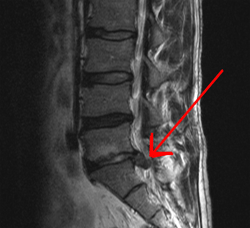

التشخيص الكامل عادة من خلال مزيج من التاريخ الطبي للمريض، والفحص البدني، وعند الاقتضاء، الاختبارات التشخيصية، مثل أشعة الرنين المغناطيسي أو الأشعة السينية.

- فتق القرص الفقري (انزلاق غضروفي).